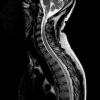

Varón de 36 años, sin antecedentes médicos ni quirúrgicos de interés, que ingresa en planta de Neurología procedente del Servicio de Urgencias por paraparesia progresiva. El cuadro se inició 3 meses antes del ingreso con dolor dorsal bajo...

Caso completo | PDF

Neurología: Neurooncología | Patología de raquisEtiología: NeoplasiasDiagnóstico final: LINFOMA DE HODGKIN (variante predominio linfocítico)Nivel de certeza: